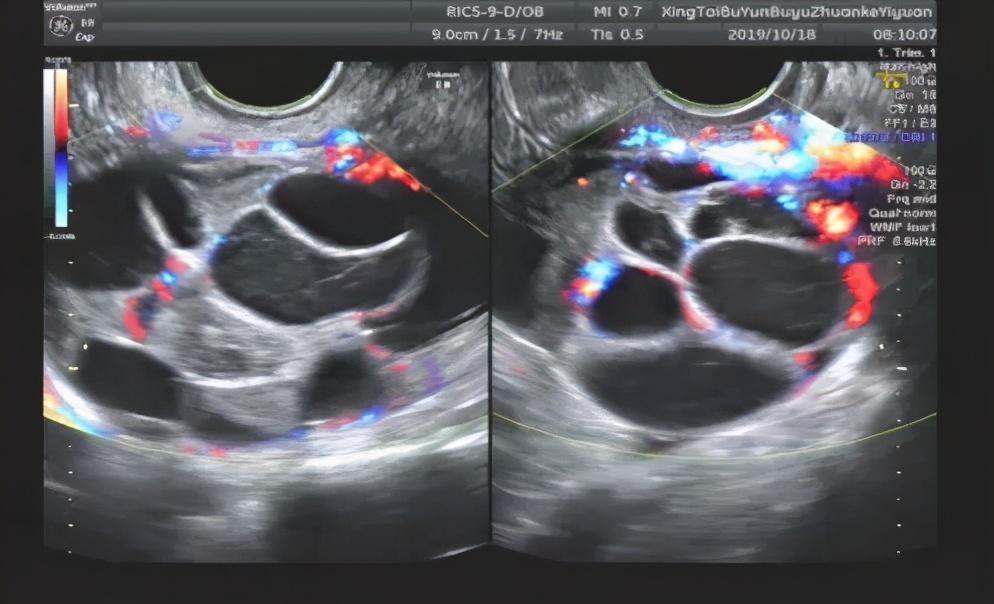

From healthjade.com

Polycystic Ovaries Symptoms, Diagnosis, Treatment, Ultrasound and Diet Can Eggs Be Damaged In Ovaries After the hormone treatment has stimulated the ovaries to produce more eggs, those eggs must be retrieved. The number and quality of. The condition often leads to infertility. It takes an enormous amount of energy for an egg to process chromosomes and mature. Potential risks associated with egg retrieval. Early trials (6) have proven that by preponing the time of. Can Eggs Be Damaged In Ovaries.